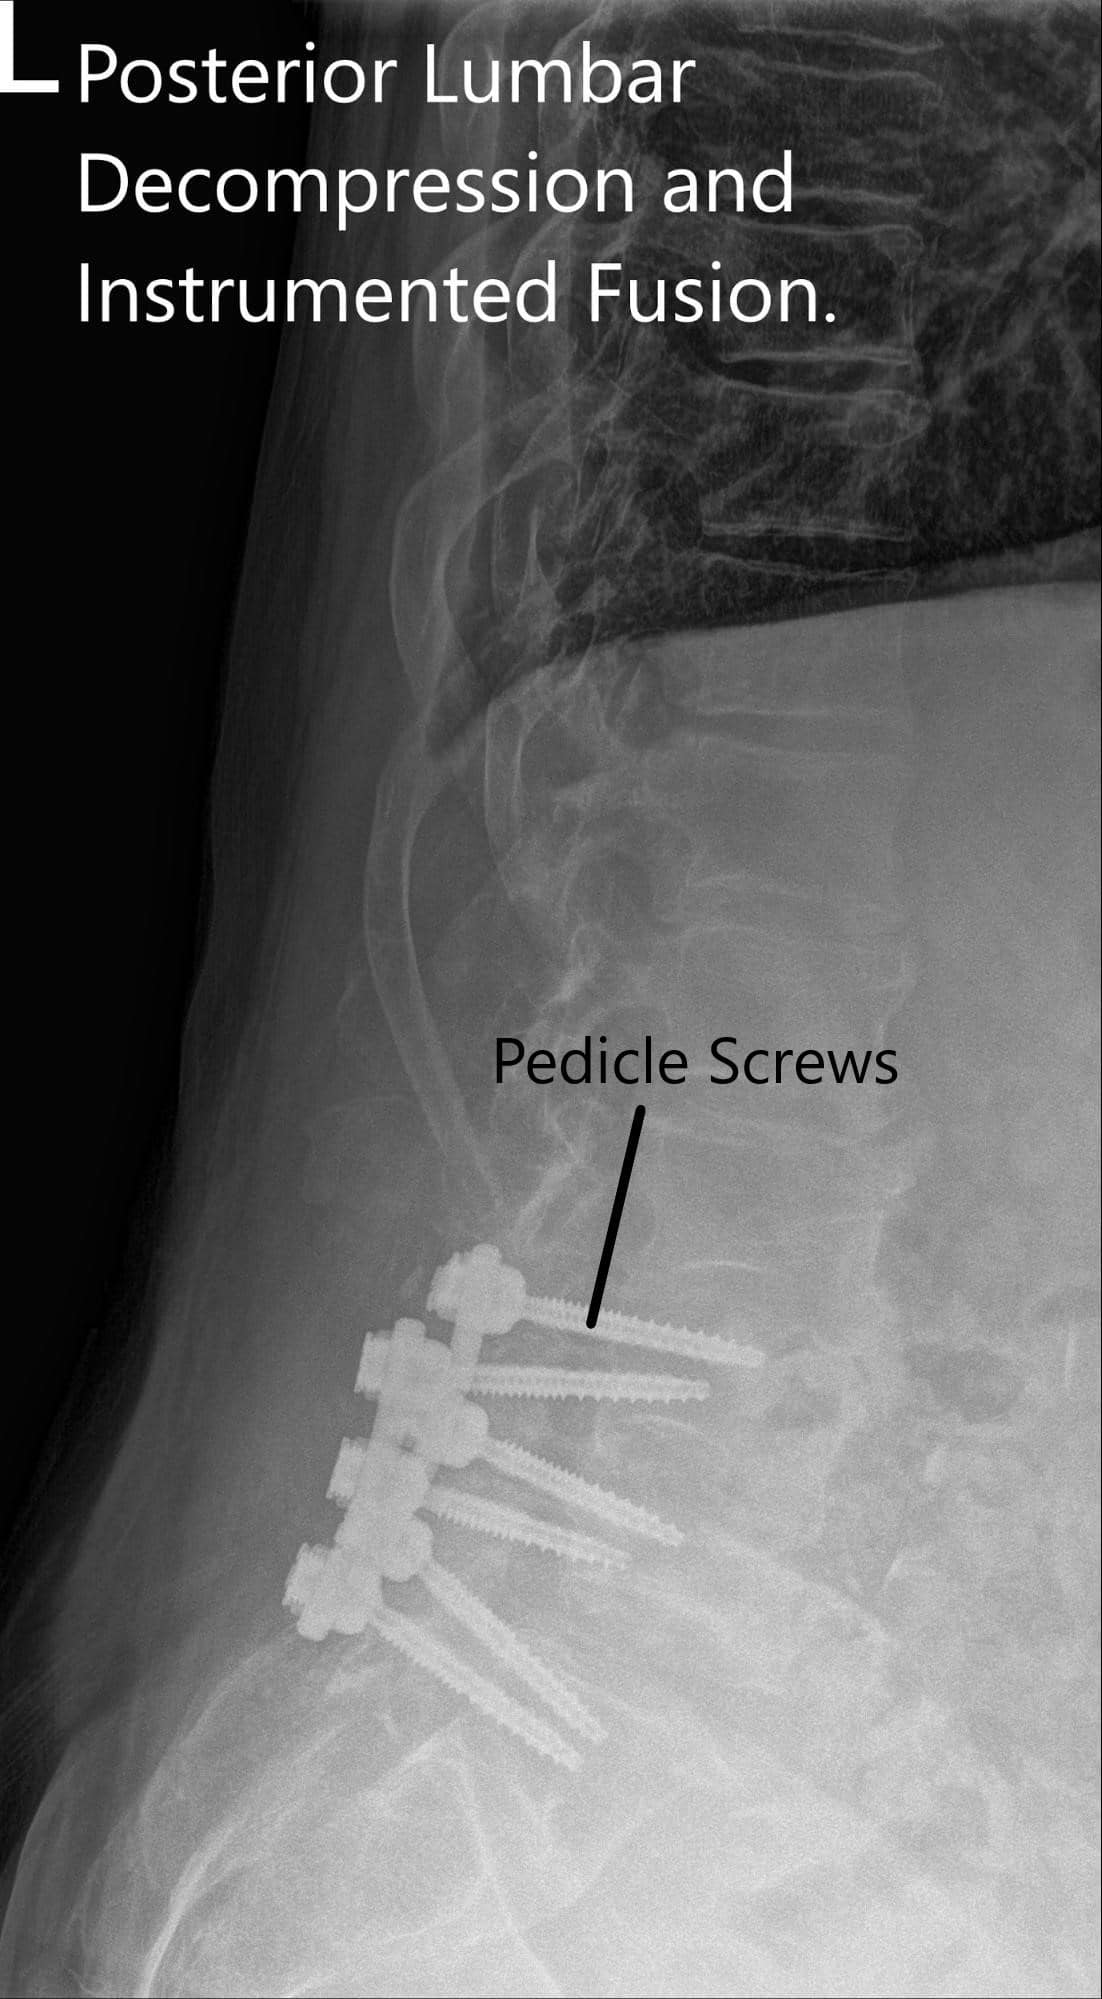

The patient agreed with the plan of Decomp L3-S1, separation surgery, Pedicle screw fixation, and posterolateral fusion L4-S1 using local autograft and cancellous chips and bone allograft.

The screws were lined and rods were placed on both sides and tightened to the screw heads. The final pictures of the screw were taken with C-arm and saved. Hemostasis was achieved. Vancomycin antibiotic was sprinkled into the wound. Considering the durotomy a deep suction drain was not put. The closure was done in layers. Two suprafascial drains were put. The counts were completed, checked, and correct at the end of the procedure. The patient was transferred into a supine position on the bed, extubated, and moved to the postoperative care unit in a stable condition.

Postoperative X-ray showing AP and Lateral Views.